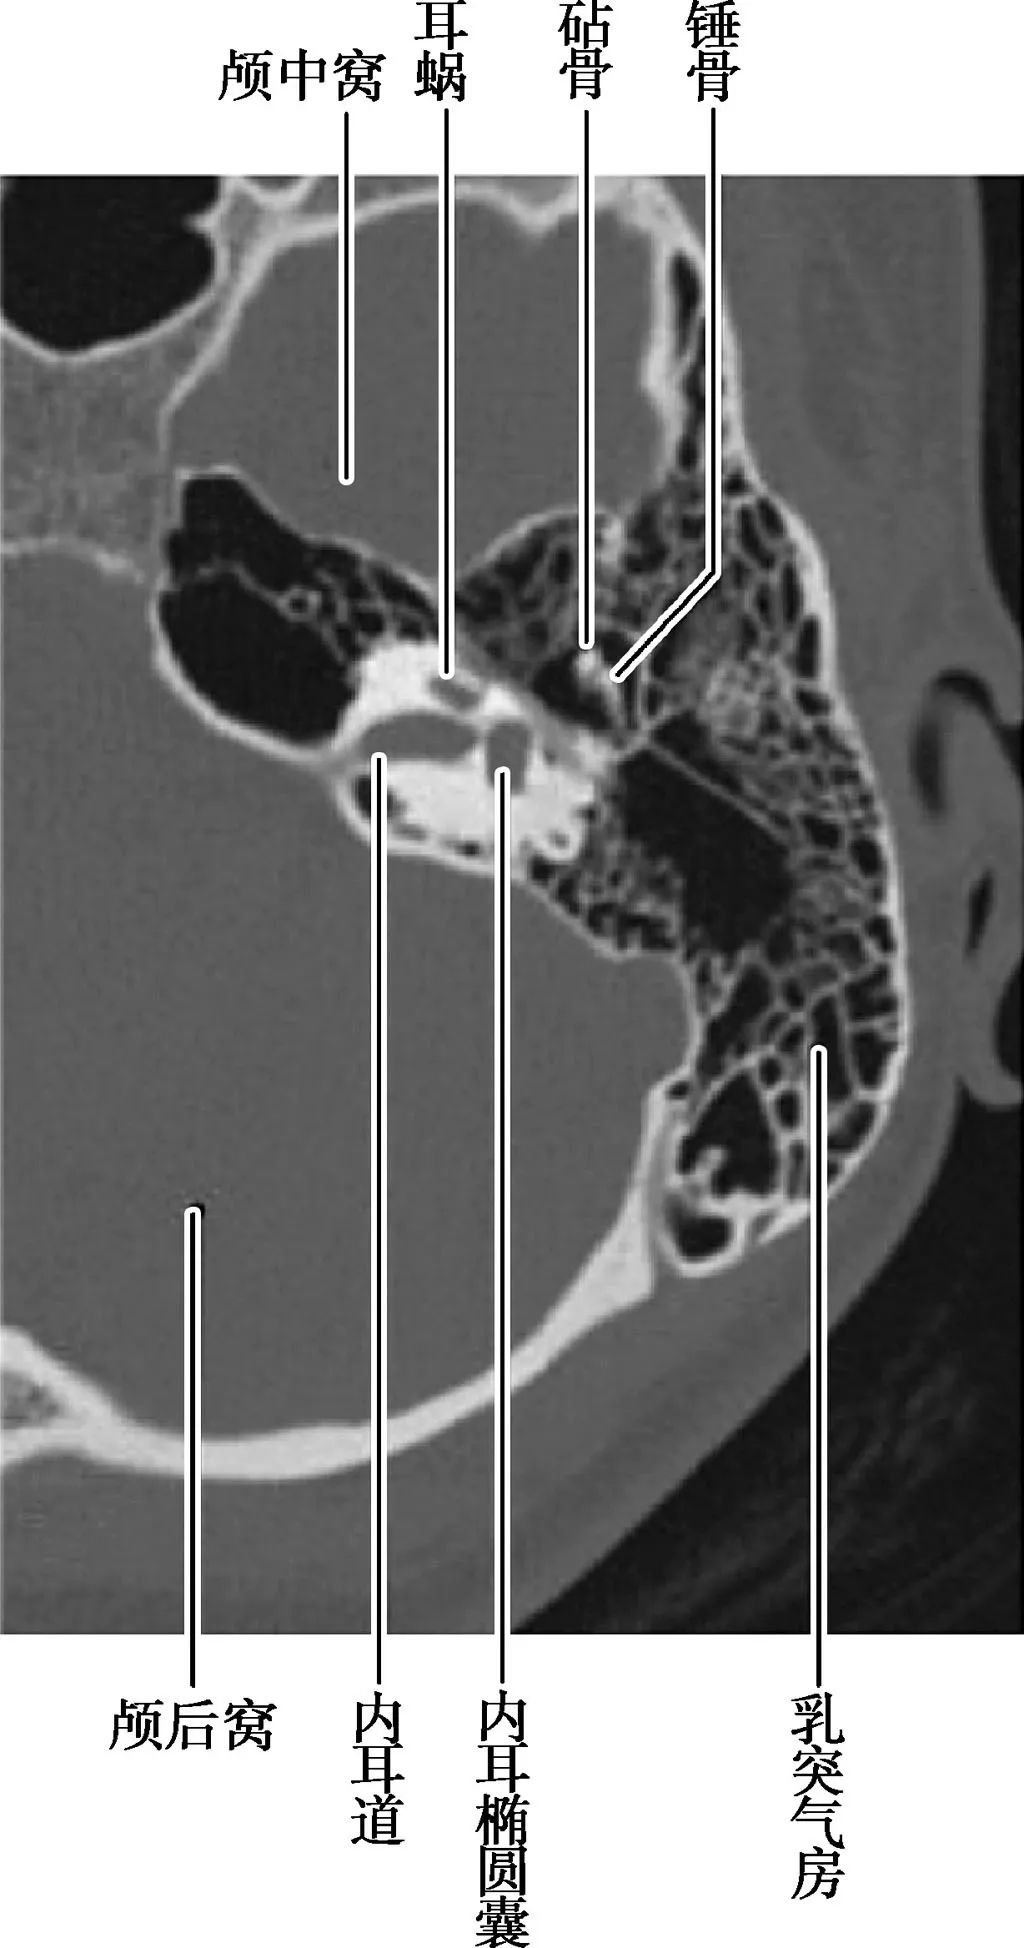

局部结构

(薄层CT)

(CT矢状面)

A.耳蜗层面;B.前庭层面;C.面神经管乳突段层面1.颈静脉球;2.内耳道;3.耳蜗;4.前庭导水管;5.后骨半规管;6.总骨脚;7.上骨半规管;8.前庭;9.面神经管迷路段;10.鼓膜张肌;11.圆窗;12.外骨半规管;13.砧骨长脚;14.锤骨颈;15.面神经管乳突段